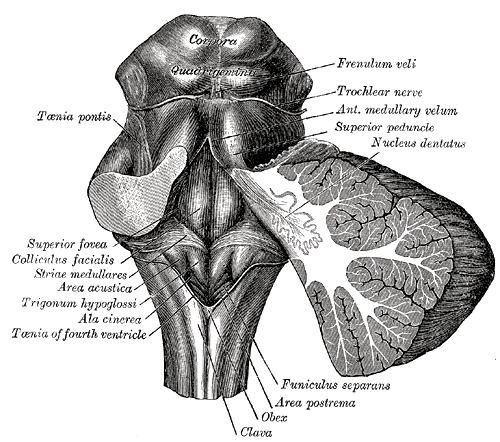

Hypoglossal Trigone. – Google Search | Anatomy and physiology, Anatomy …

Hypoglossal trigone – Alchetron, The Free Social Encyclopedia